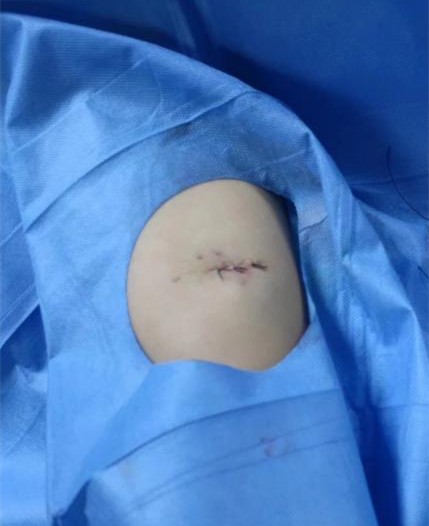

温碧玲副主任护师通过B超引导赛丁格技术,辅助心腔内电图定位技术,将导管尖端管道精准到达上腔静脉下1/3段,再由乐文俊副主任医师于局麻下将港座埋植于右上臂肘上5厘米处后缝合,患者全术程生命体征平稳,术后步行离开置管室,解决了罗先生的大难题。